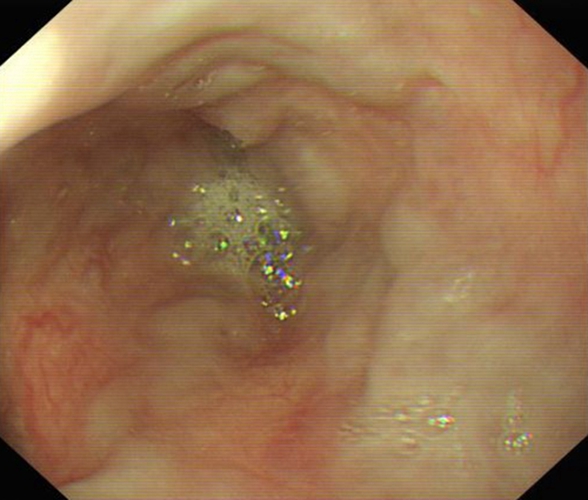

急性胃炎圖片

急性胃炎陽性表現

急性胃炎陽性的表現

急性胃炎